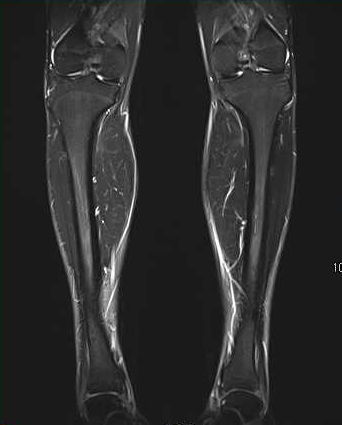

MRI撮影

磁気共鳴画像(Magnetic Resonance Imaging)の略です。 エックス線は使用せず,強い磁石と電磁波を使って体内の状態を断面像として描写する検査です。単純レントゲン撮影では分からない微細な骨折、疲労骨折や圧迫骨折の新旧など判断できます。